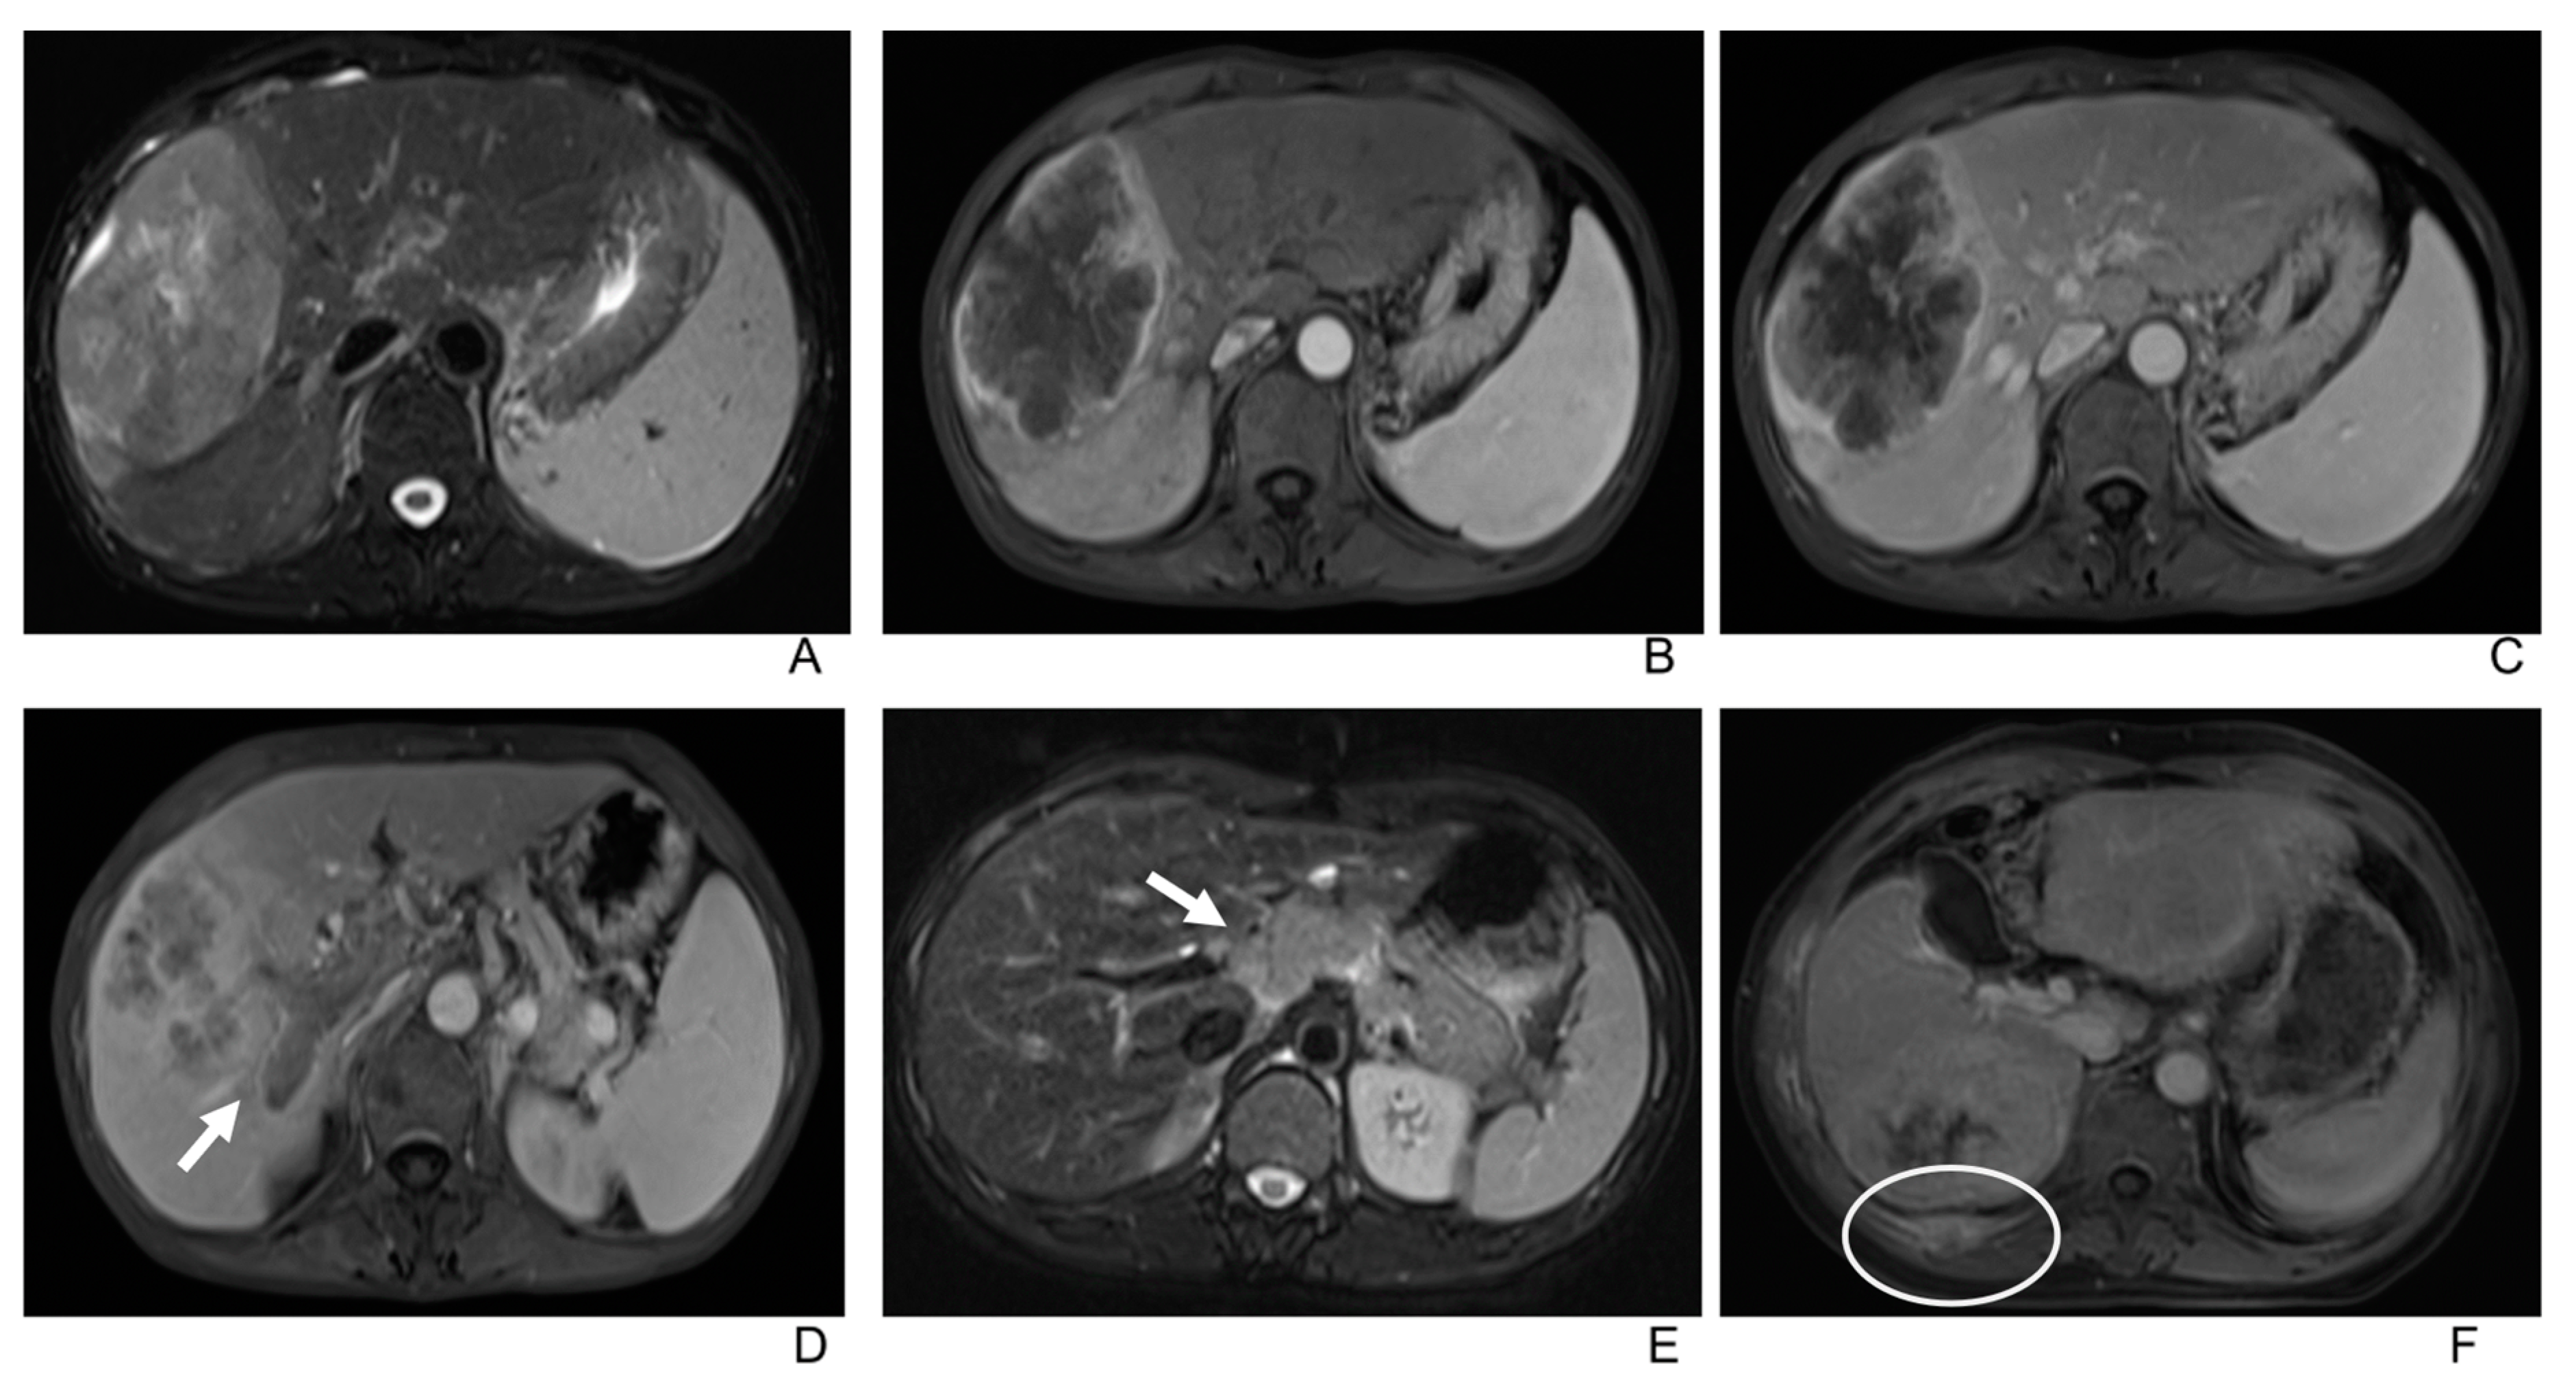

- (i)

- Type A: Rim enhancement, characteristic of typical iCCA.

- (ii)

- Type B: Nonrim arterial phase hyperenhancement with wash-out in PVP or DP, which resembles the “rapid wash-in and wash-out” seen in typical HCC.

- (iii)

- Type C: Nonrim arterial phase hyperenhancement with either consistent enhancement or isointensity in PVP or DP, or “rapid wash-in without wash-out”

| Dynamic enhancement patterns | |

| Type A a | 21(55%) |

| Type B b | 10(26%) |

| Type C c | 7(18%) |

| Capsular enhancement | 22/38(58%) |

| Type A/Type B/Type C | 13/9/0/(62%/90%/0) |